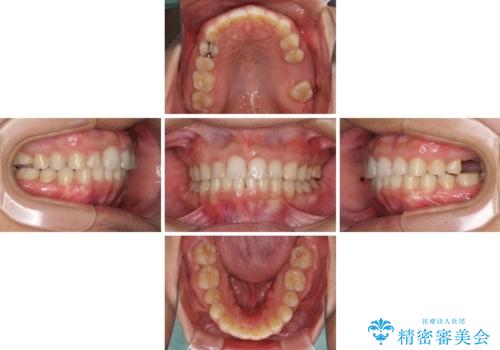

- 深い咬み合わせと前歯のデコボコ、奥歯の欠損を気にして来院された患者様です。

歯列矯正はインビザラインを使用し、矯正治療中の適切な時期に奥歯の欠損部位にインプラントを埋入することとしました。

矯正治療とインプラント治療を同じ歯科医師が担当することで、通常見られるような複数医院を行き来する煩雑さや、複数担当医の見解の違いによる治療の遅滞といった煩わしさは一切なく、スムーズに治療を進めることができました。